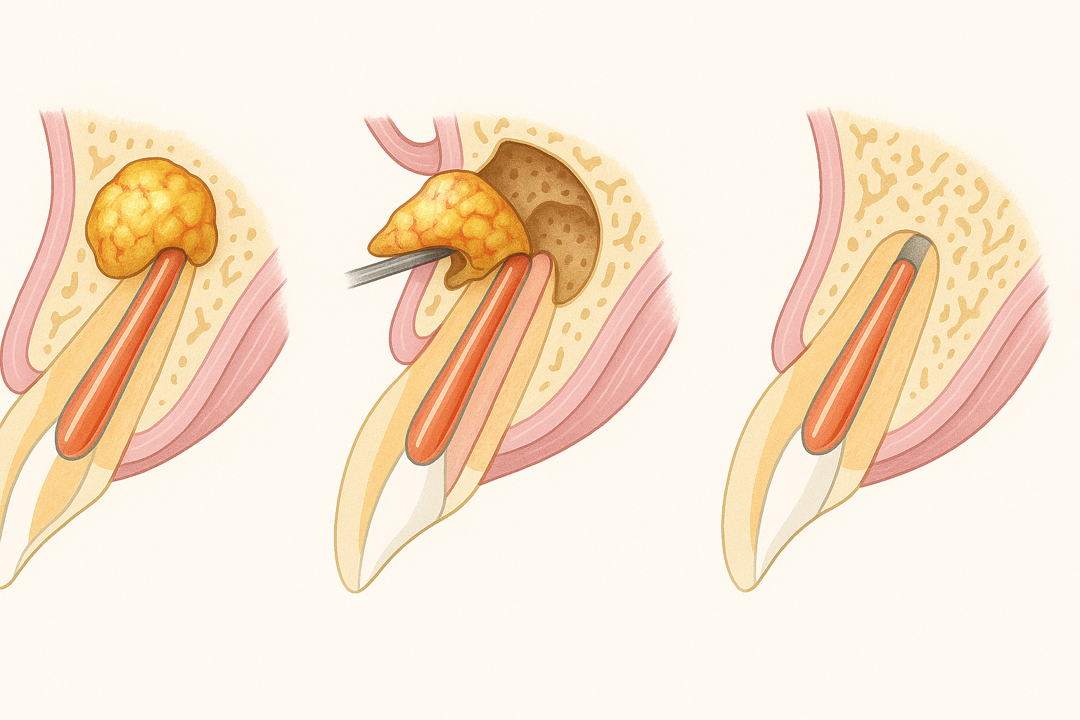

- 歯根端切除術

歯の根の先端に膿がたまることがあります。

この場合も「抜歯宣告」がされるケースです。

この場合であっても当法人では「歯根端切除術」という治療法で、抜歯せずに治せることがあります。

「歯根端切除術」は、歯茎の外側を外科的に切開し、炎症を引き起こしている歯の根と膿の袋を完全に取り除く治療法です。